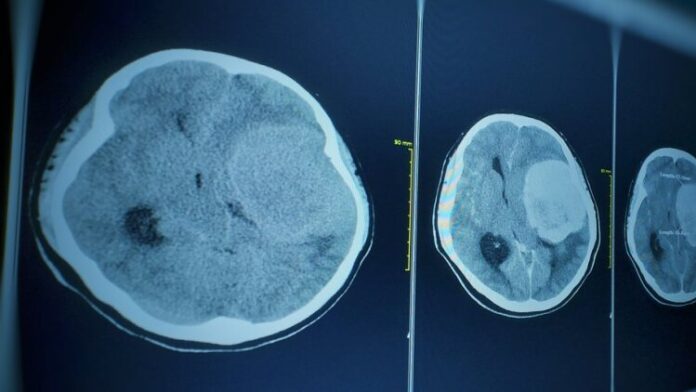

Το θύμα, που δεν είχε υποκείμενα νοσήματα, πέθανε από νεγλαιρίαση – γνωστή επίσης ως πρωτογενής αμοιβαδική μηνιγγοεγκεφαλίτιδα (primary amoebic meningoencephalitis ή PAM) – μια σπάνια λοίμωξη του εγκεφάλου, η οποία προκαλείται από την αμοιβάδα Naegleria fowleri.